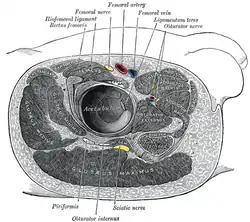

Structures surrounding right hip-joint. Gluteus medius muscle (shown in green text)

Gluteus medius muscle (shown in green text)

- Cross section image: pelvis/pelvis-e12-15—Plastination Laboratory at the Medical University of Vienna